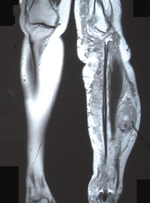

МРТ левой голени: злокачественная опухоль оболочки большеберцового нерва при синдроме Реклингхаузена (NF-1).